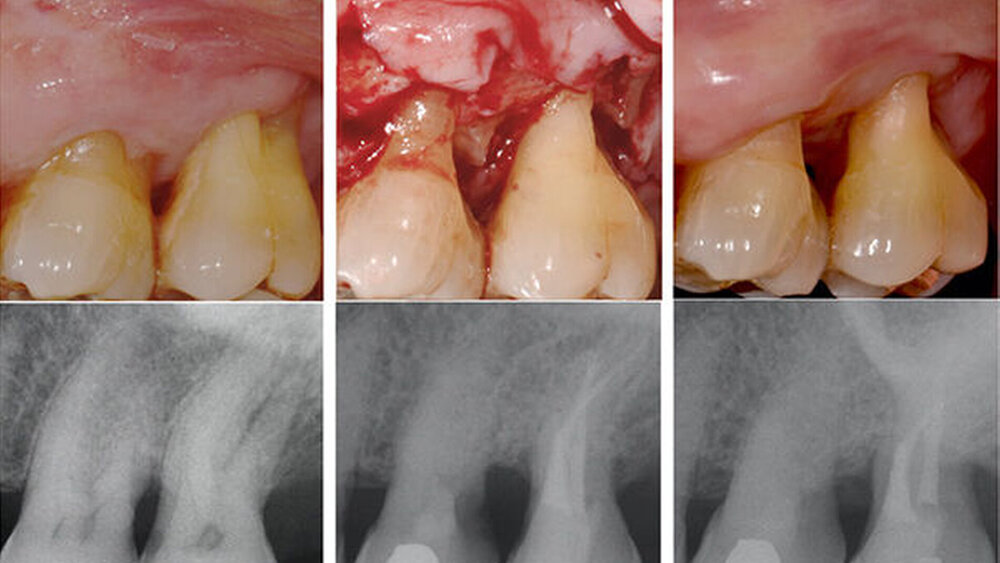

stellten die Bonner Wissenschaftler eine neuartige Methode der Wurzelresektion an furkationsbefallenen, vitalen Zähnen vor. Insgesamt resezierten sie bei 15 Zähnen (11 Patienten zwischen 39 und 73 Jahren) mit entweder multiplen Grad II oder aber mit Grad III Furkationsbefall jeweils eine Wurzel, die rundum vertikalen Knochenverlust sowie große Sondierungstiefen mit Blutung aufwies. Die betroffenen Zähne waren maximal Grad I gelockert.

Vier Wochen vor der Resektion führten die Bonner Spezialisten eine tiefe Pulpotomie unter aseptischen Bedingungen unter Kofferdam und mit Einsatz eines OP-Mikroskops durch. Nach Blutstillung deckten sie die Wurzelpulpa mit Kalziumsilikatzement (Biodentine™, Septodont) und dichteten den Zugang danach mit Komposit ab. War die Vitalitätstestung nach vier Wochen positiv, resezierten sie die Wurzel minimalinvasiv mit piezochirurgischen Instrumenten unter kontinuierlicher Kochsalzspülung. Intraoperativ reinigten sie die verbleibenden Wurzeloberflächen und entfernten sämtliches Granulationsgewebe.

Die Wundheilung verlief komplikationslos, die Patienten verspürten lediglich eine Woche lang eine Hypersensitivität des entsprechenden Zahnes und nahmen danach regelmäßig an der UPT teil. Alle Zähne waren nach ihrem jeweiligen Beobachtungszeitraum (drei bis sieben Jahre) sensibel auf Vitalitätsproben und mit stabilem klinischen Attachmentniveau in situ. Die Sonderungstiefen waren deutlich reduziert, der Furkationsbefall beseitigt oder maximal Grad I. Die Patienten waren mit dem Ergebnis durchweg zufrieden.

Die histologische Untersuchung an Querschnitten der resezierten Wurzeln aus dem mittlerem Wurzeldrittel zeigte alle Merkmale eines funktionellen Pulpa-Dentin-Komplexes.